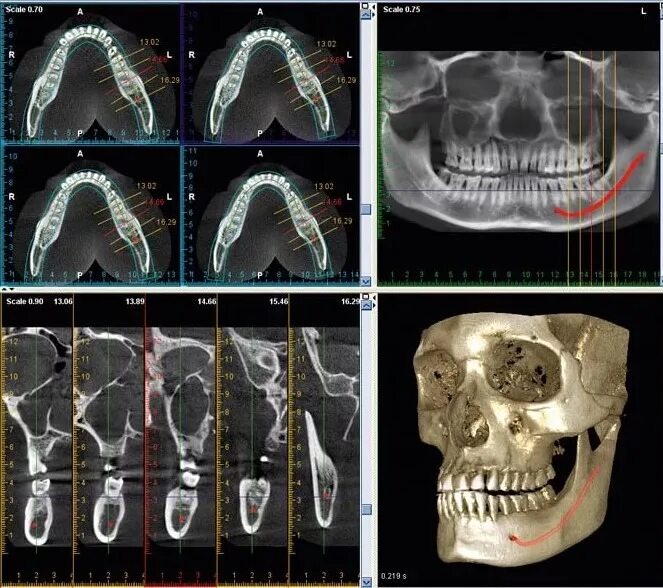

Кл кт